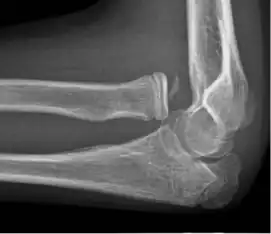

- Elbow

Prognosis varies depending on the location and extent of the dislocation. The prognosis of a shoulder dislocation is dependent on various factors including age, strength, connective tissue health and severity of the injury causing the dislocation.[23] There is a good prognosis in simple elbow dislocations in younger people. Older people report more pain and stiffness on average.[23] Wrist dislocations are often difficult to manage due to the difficulty in healing the small bones in the wrist.[23] Finger displacement towards the back of the hand is often irreducible due to associated injuries, while finger displacement towards the palm of the hand is more readily reducible.[23] Overall, recovering from a joint dislocation can range from a few weeks to months, depending on the severity of the injury.[4]